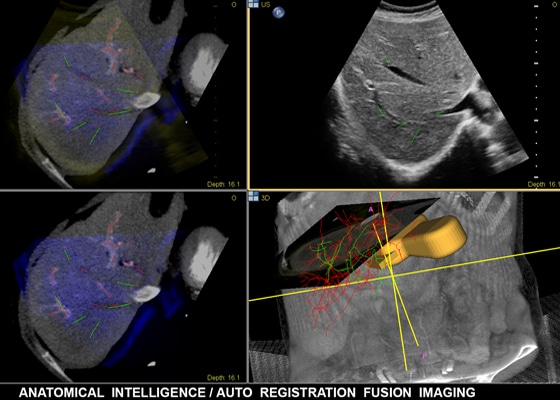

Anatomische Intelligenz wendet adaptive Systemintelligenz mit anatomischen 3D-Modellen auf die Ultraschalldaten eines Patienten an, um schnell und einfach reproduzierbare Ergebnisse zu liefern. Mit fortschrittlichen Funktionen für die Organmodellierung, Erstellung von Schnittbildern und Quantifizierung ermöglicht die Anatomische Intelligenz eine einfachere Durchführung und bessere Reproduzierbarkeit von Ultraschalluntersuchungen und liefert gleichzeitig aussagekräftige klinische Ergebnisse, um den wirtschaftlichen und klinischen Herausforderungen der heutigen Gesundheitsumgebung gerecht zu werden.

Anatomische Intelligenz kommt bei Philips Bildgebungslösungen wie EPIQ Affiniti und EchoNavigator zum Einsatz und stattet Klinikteams mit ausgereiften aber dennoch benutzerfreundlichen Verarbeitungstools aus. Dabei ermöglicht sie die zuverlässige Identifizierung von anatomischen Strukturen und Anomalien die Beurteilung des Krankheitsstatus die Ermittlung der passenden Behandlung und die Durchführung geführter Eingriffe in kürzester Zeit.

SmartFusion sorgt für einen besseren Einblick und hohe Sicherheit bei Diagnose und Behandlung; EchoNavigator verknüpft Live-3D-TEE und Echtzeit-Radiographie, damit Implantate in 3D dargestellt und dadurch intuitiv in kürzerer Zeit eingebracht werden kann.